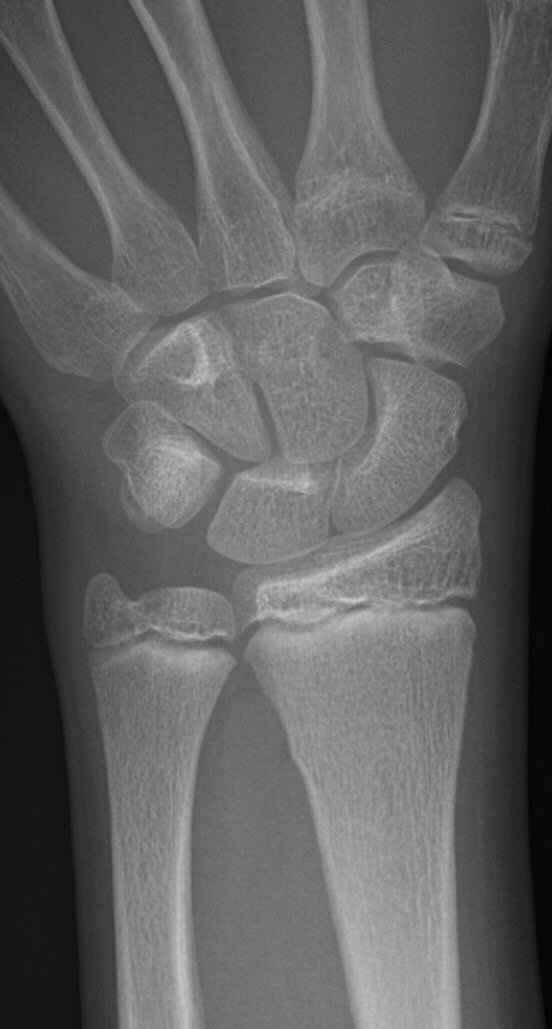

Dorsalbockad distal radiusfyseolys Salter-Harris typ 2 före och efter reposition